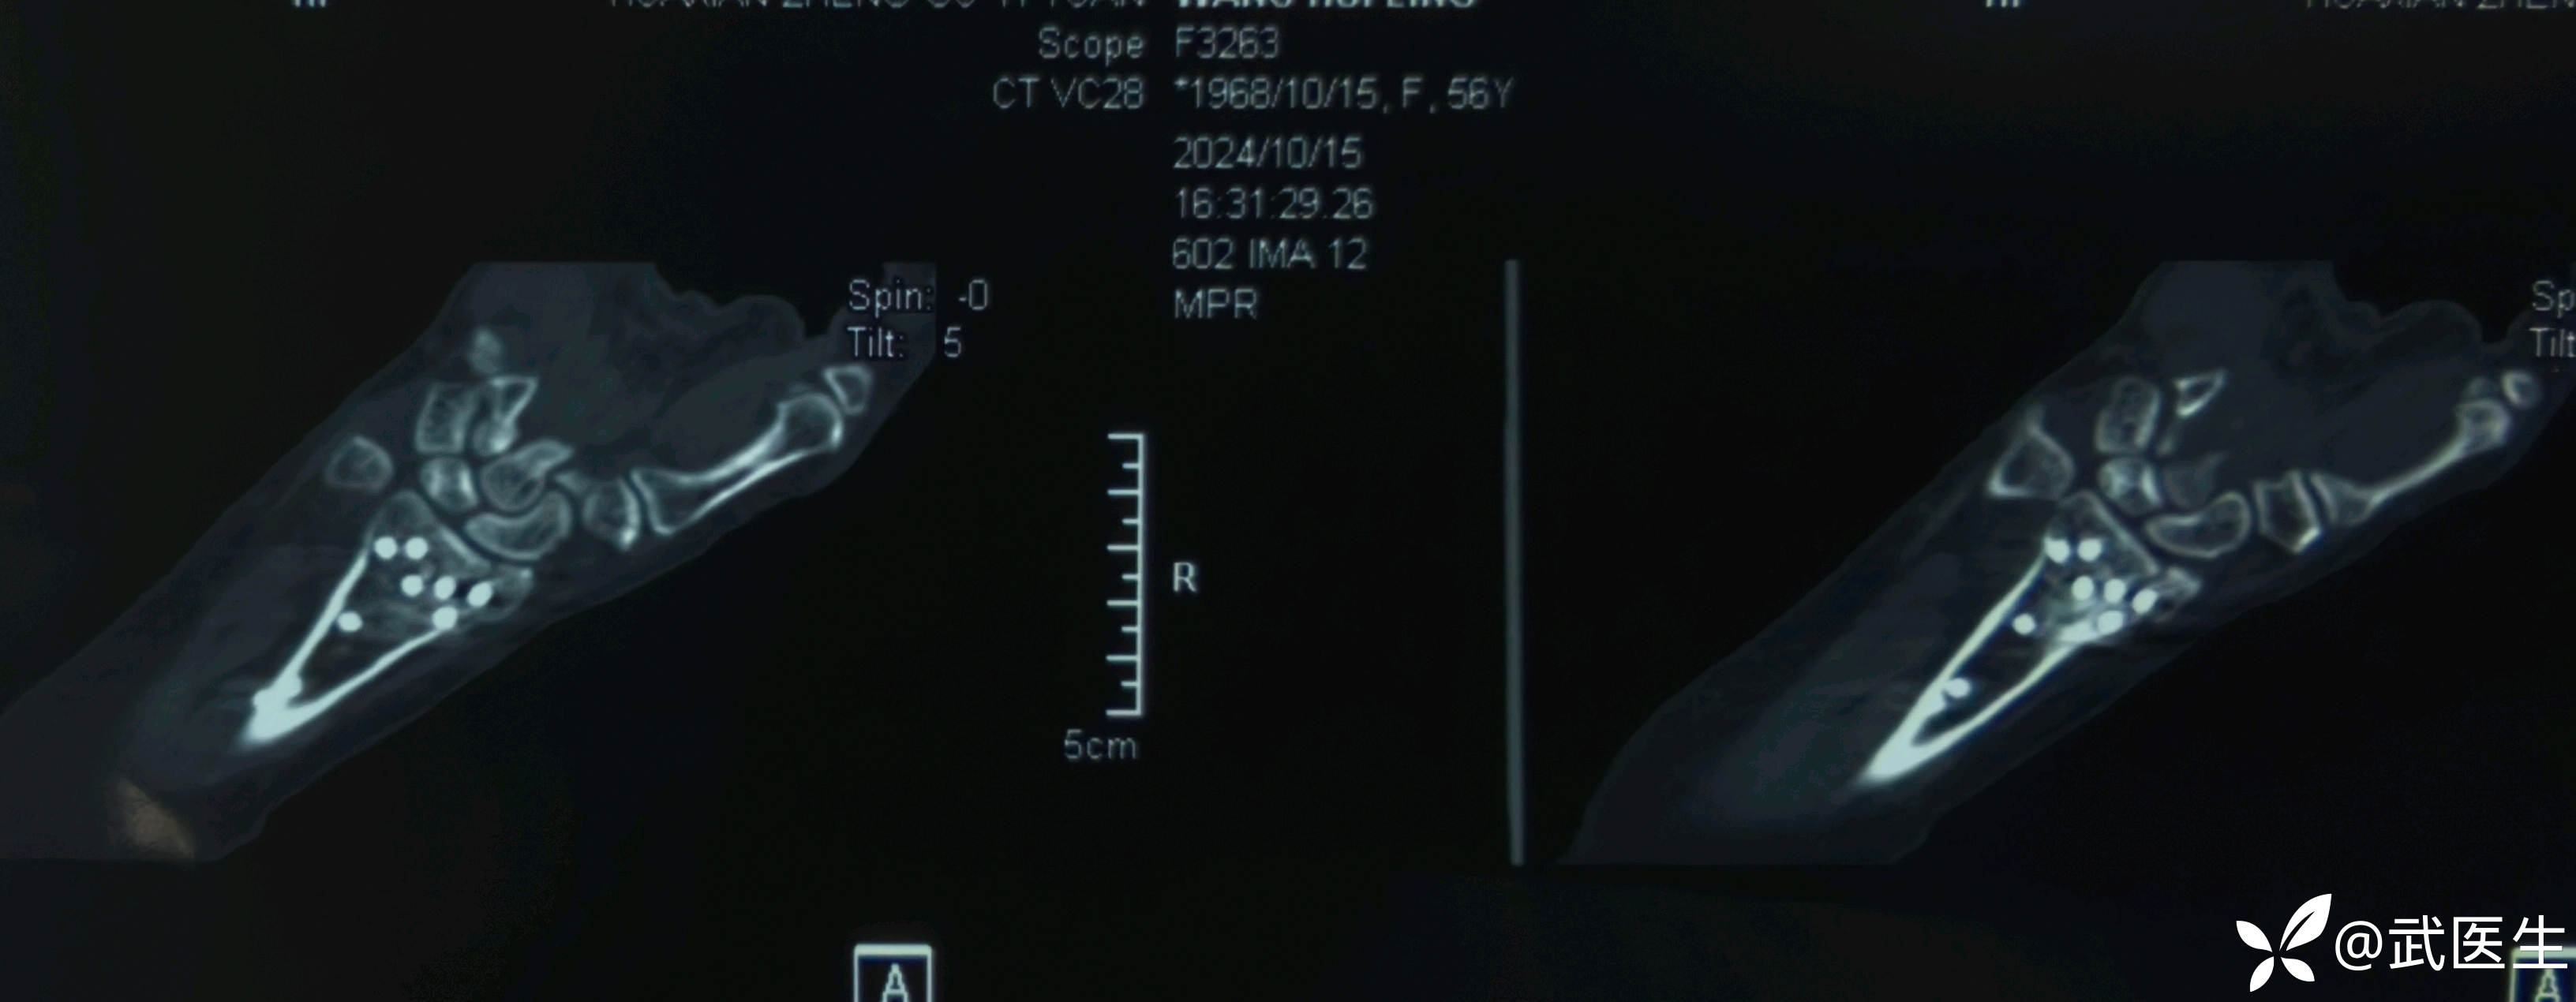

影像学检查如下

腕关节片子系外院带来

【临床诊断】:右肱骨外科颈四部分骨折脱位,左桡骨远端骨折伴桡腕关节半脱位。钩骨骨折。头面部软组织损伤。